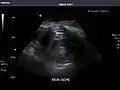

Renal ultrasonography

Ultrasonography of the kidneys is essential in the diagnosis and management of kidney-related diseases. The kidneys are easily examined, and most pathological changes in the kidneys are distinguishable with ultrasound.[7]

Right kidney

Kidneys: Right and left kidneys measure 11.5 cm and 12 cm in length respectively. No hydronephrosis. Small left lower pole kidney cyst.